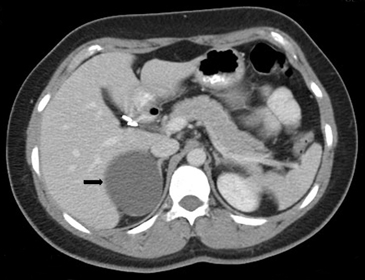

Tanto las lesiones benignas como malignas pueden presentar una atenuación heterogénea, especialmente en fases contrastadas, pero la presencia de grandes focos necróticos son mas bien orientadores de malignidad (Figura 8 a y b).

A

B

En TC sin contraste por lo general se observa una masa heterogénea, especialmente en caso de lesiones de mayor tamaño por la presencia de necrosis. Entre un 19 a 33% de los casos se identifican calcificaciones. Luego de la administración de contraste su refuerzo es heterogéneo y su patrón de lavado es consistente con una enfermedad maligna (Figura 22).

Los sitios más habituales de metástasis son hígado, pulmón, además de la invasión de las estructuras vasculares adyacentes, especialmente de la vena cava inferior, hallazgo que constituye una consideración fundamental al momento de planificar el abordaje quirúrgico (Figura 23 a y b).